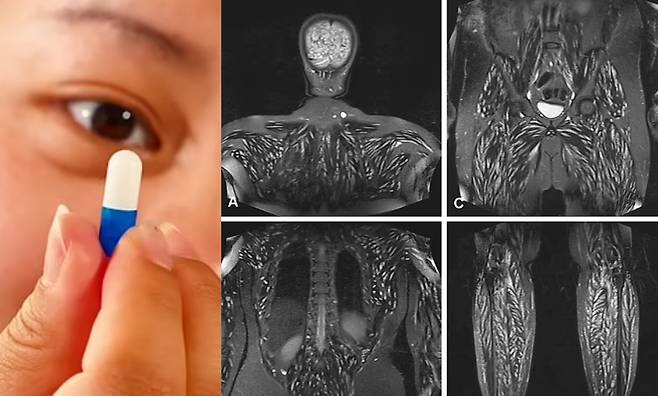

![건강상 문제를 일으킨 것은 돼지 촌충이었다. 이 기생충은 알을 몸속으로 방출해 혈류를 통해 근육과 뇌에 퍼져 낭포충증을 일으킨다. 이 알들은 주로 무해하지만 뇌와 같은 민감한 조직에 발생하면 문제가 된다. [사진= 영국 데일리메일 보도 갈무리 /출처= 유튜브 Chubbyemu]](https://img2.daumcdn.net/thumb/R658x0.q70/?fname=https://t1.daumcdn.net/news/202410/16/KorMedi/20241016113816448qvkn.jpg)

하지만 몇 주 후, 턱 아래에 이상한 혹이 생기기 시작했고, 만졌더니 바로 기절하고 깨어났다. 이후 심한 두통과 함께 두개골에 강한 압박을 느꼈다. 이상함을 감지한 그는 병원을 찾았고, 척수액에 비정상적인 압력이 있다는 진단을 받았다. 그 원인이 무엇인지 찾으려 여러 검사를 받았지만 밝혀진 게 없었다. 약물로 부종을 억제한 뒤 퇴원했다.

증상은 바로 재발했다. 기억 상실 및 두통과 같은 새로운 문제가 발생했다. 다시 병원을 찾은 TE는 두뇌에 여러 병변이 발견됐고, 목, 얼굴, 혀, 간 등 온몸 곳곳에서 하얀 병변이 나타났다.

상황이 심각해지자 TE는 의료진에게 자신이 체중 감량을 위해 촌충 알을 섭취한 사실을 털어놓았다. 그가 섭취한 알은 소 촌충(Taenia saginata)과 돼지 촌충(Taenia solium) 등 두 가지 기생충에 속한 것으로 밝혀졌다. 소 촌충은 주로 소고기에서 발견되며, TE가 전에 화장실에서 변을 본 후 발견한 직사각형 모양의 갈색 알과 일치했다.

건강상 문제를 일으킨 것은 돼지 촌충이었다. 이 기생충은 알을 몸속으로 방출해 혈류를 통해 근육과 뇌에 퍼져 낭포충증을 일으킨다. 주로 무해하지만 뇌와 같은 민감한 조직에 발생하면 문제가 된다.